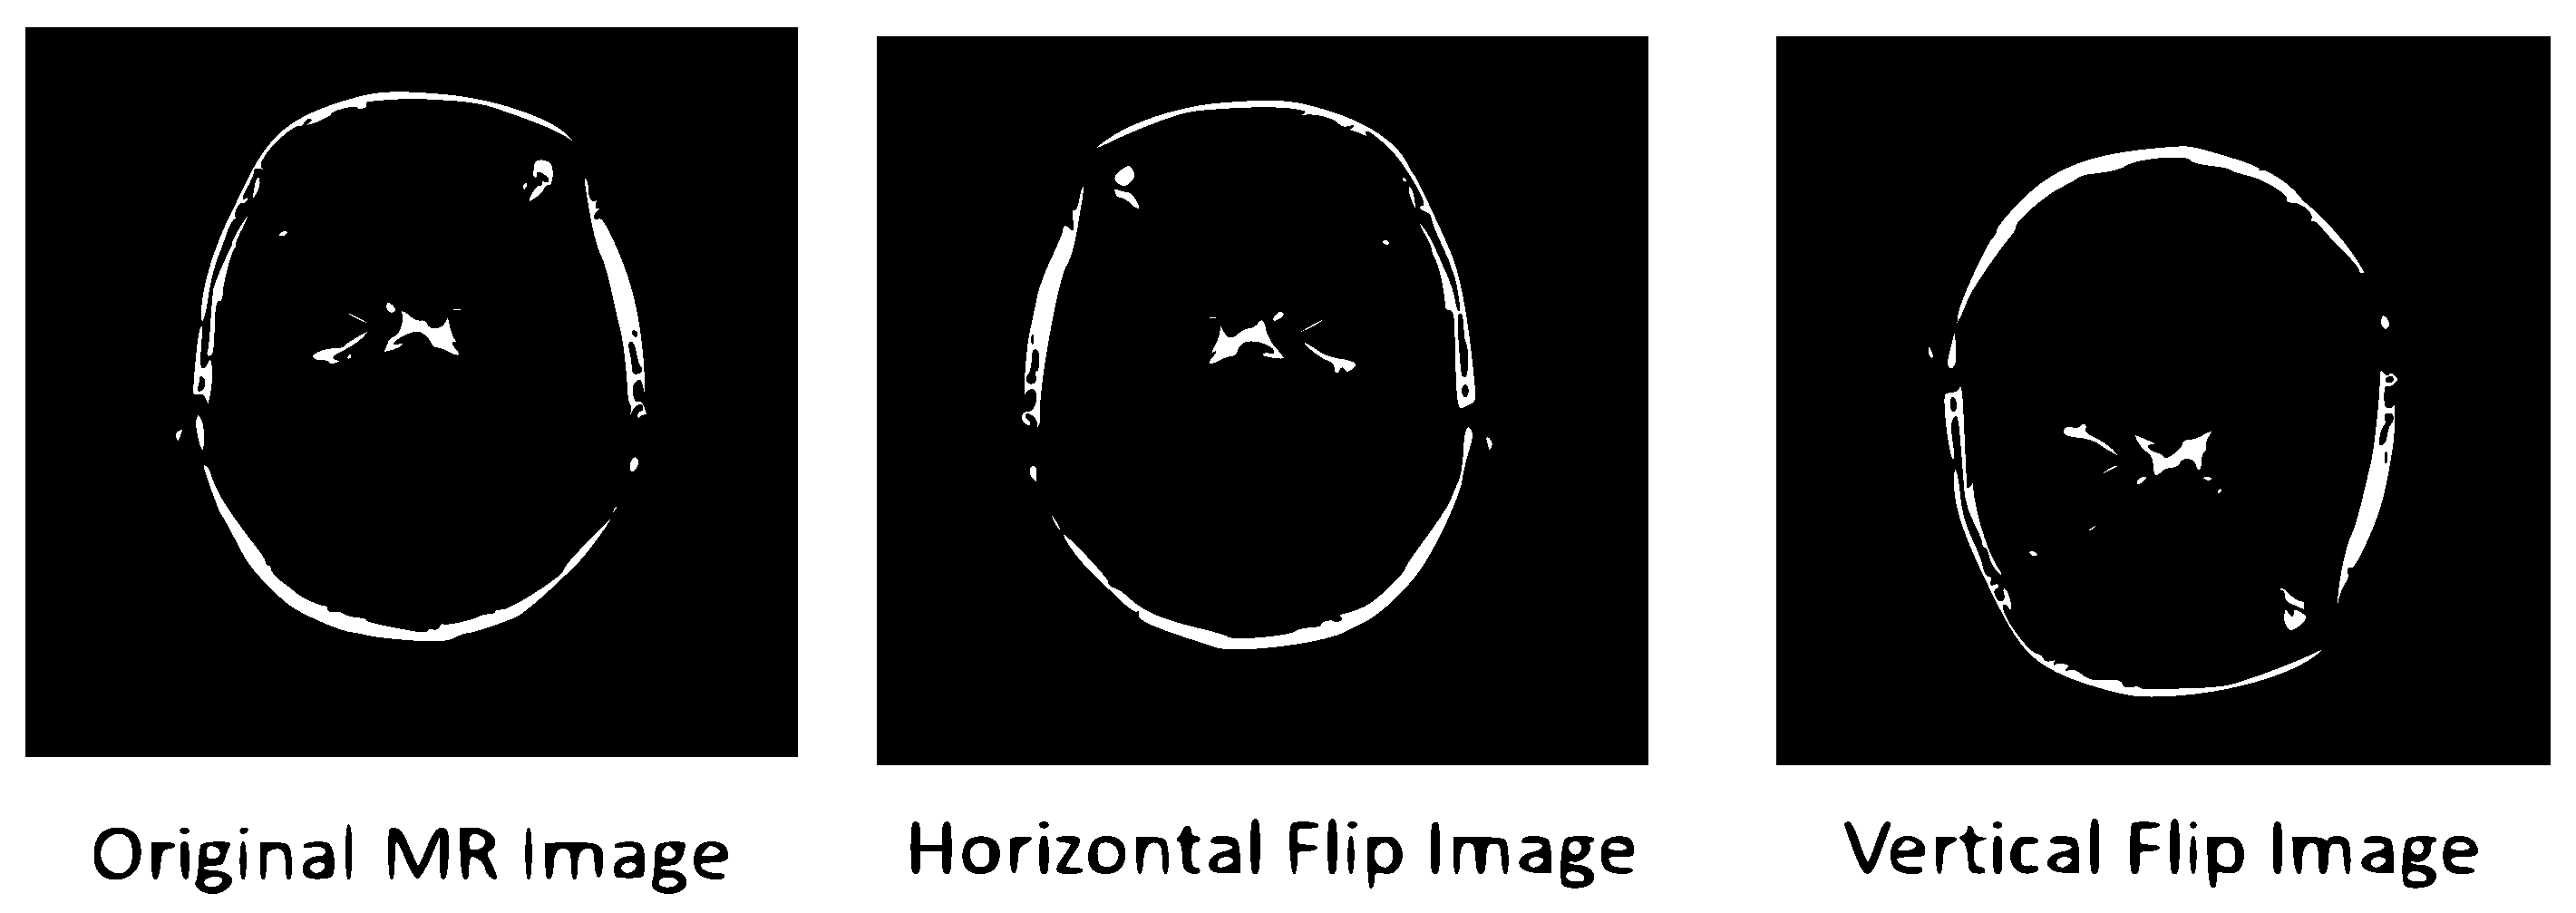

3.3. Data Preprocessing and Augmentation